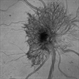

- NEOVASCULARISATION OF DISC

- Dr Shobhit chawla

- Fundus camera

- Fundus photograph of a 50 year-old male, with long-standing diabetes of 25 years. Treated with panretinal photocoagulation.